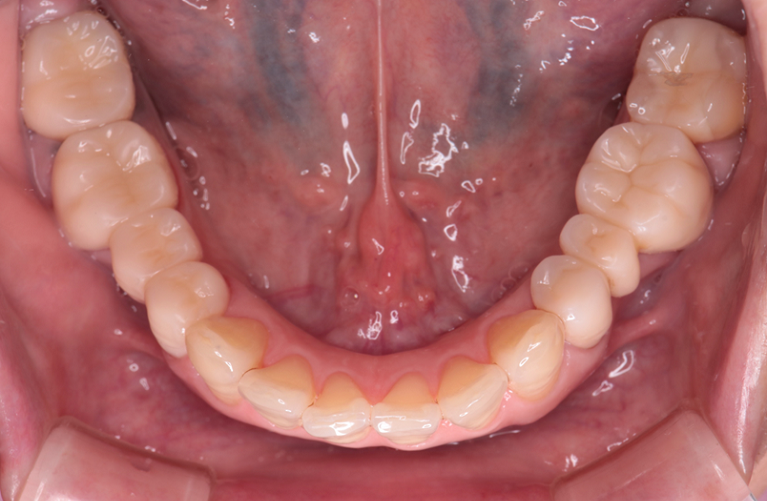

治療後

下顎